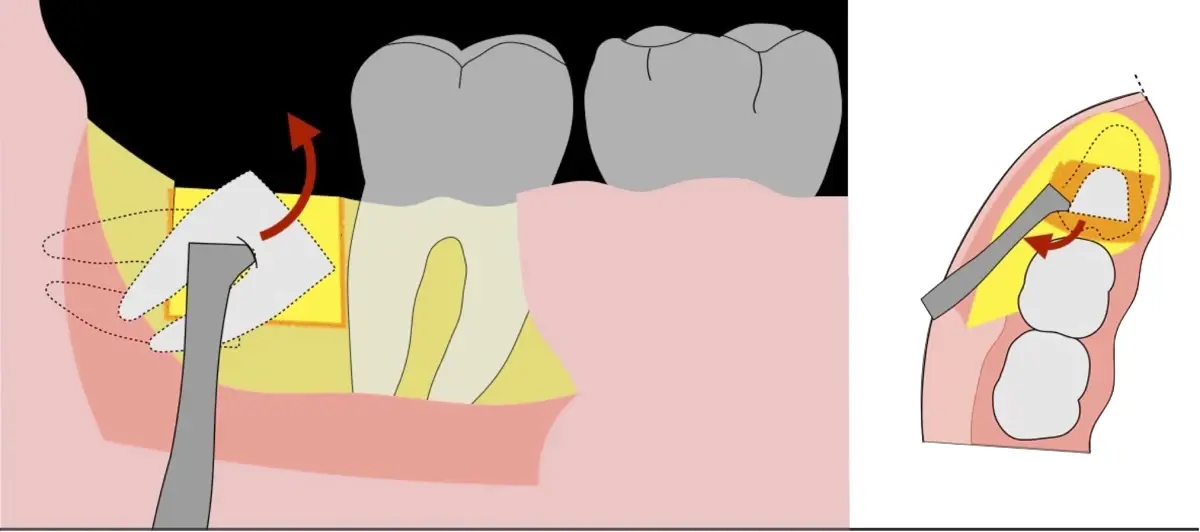

El procedimiento puede variar en su complejidad dependiendo de su ubicación, profundidad, angulación, y la densidad ósea circundante.2 Uno de los pasos más críticos y cruciales en la extracción es la osteotomía previa y concomitante al acceso quirúrgico del diente, para lo cual se utilizan diversos instrumentos como cinceles y martillos, instrumental rotatorio o de corte por ultrasonido.3

En contraste, el instrumento piezoeléctrico utiliza un corte micrométrico que retira un área de superficie mínima de hueso, y reduce el riesgo de termonecrosis marginal en comparación con las fresas rotatorias convencionales.9 Los micromovimientos mejoran la precisión en el corte y el control táctil, y eliminan las macrovibraciones que se producen con los instrumentos rotatorios.10 Su frecuencia de oscilación es la amplitud de 60-200 μm horizontalmente y de 20-60 μm en sentido vertical, lo que es muy inferior en comparación con las micro sierras oscilantes; por lo tanto, proporciona cortes de osteotomía precisos y seguros. Adicionalmente, posee vibraciones ultrasónicas que descomponen el líquido de irrigación en partículas muy pequeñas (fenómeno de cavitación, que produce un efecto hemostático y así reduce la pérdida de sangre), lo que proporciona una visión clara y sin obstáculos del campo quirúrgico11,12.

El procedimiento se inicia colocando anestesia troncular para bloqueo del nervio dentario inferior y sus ramas. Luego, se establecerá el diseño de acceso según la disposición de la molar a extraer. Para fines didácticos, se explicará cómo se realizaría la extracción de la molar de la Figura 1: se realiza una incisión horizontal a nivel de la zona retromolar hasta llegar a distal de la segunda molar, continuándose con una incisión intrasurcular hasta mesial de la segunda molar, finalizando con una incisión vertical a espesor total hasta llegar a la línea mucogingival (Figura 2).